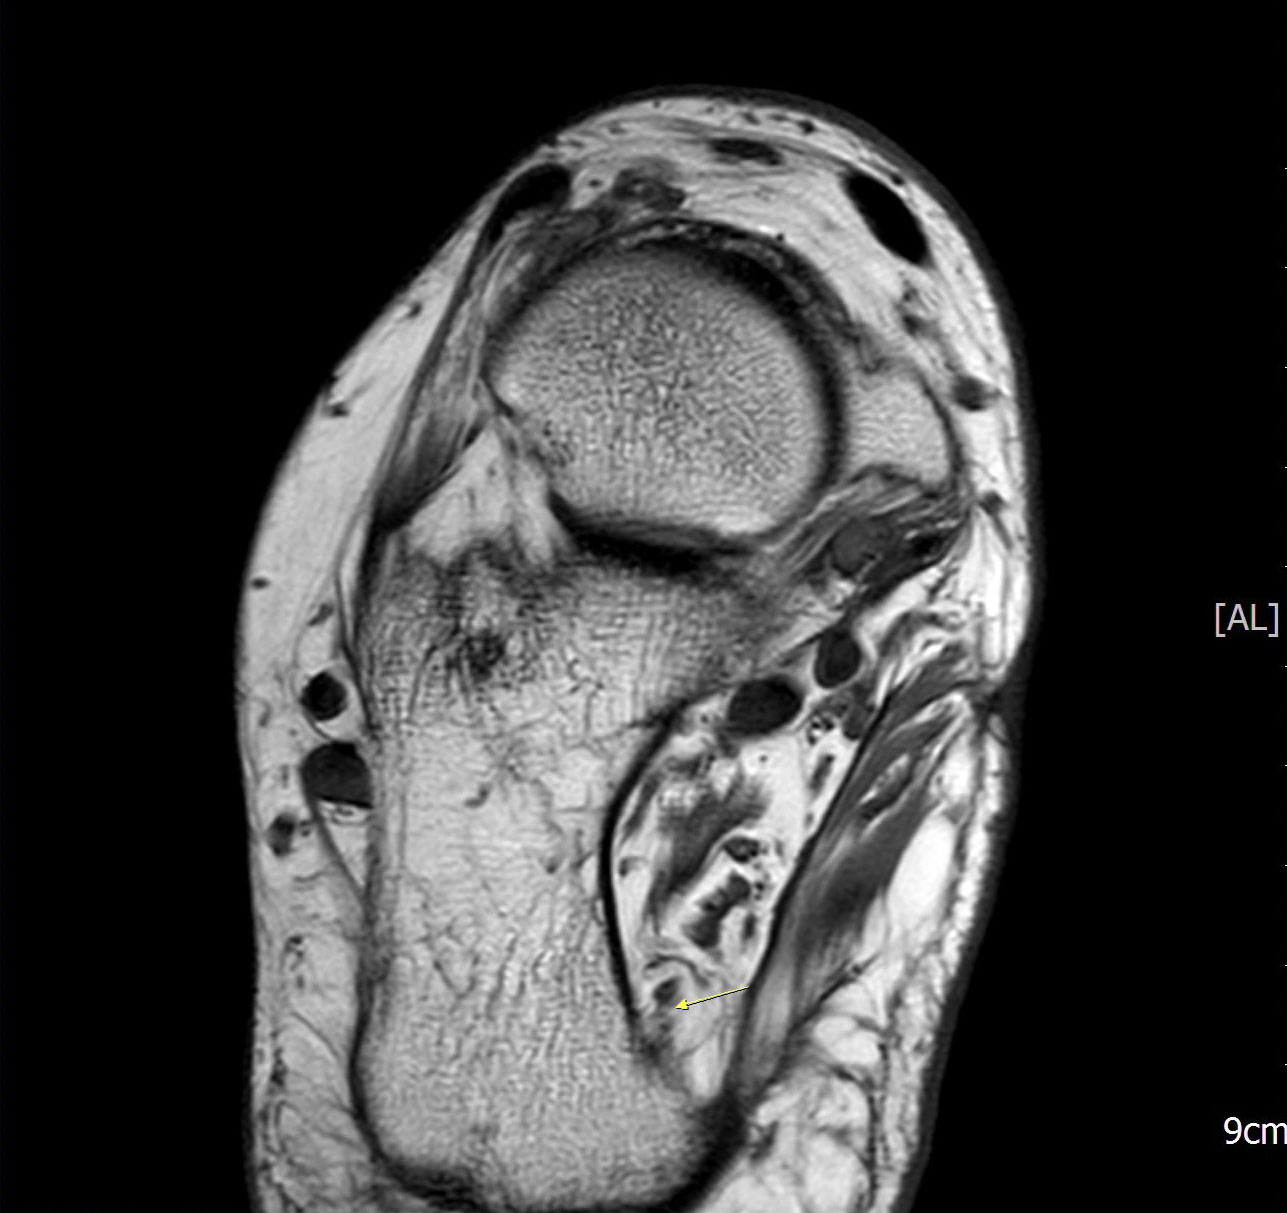

Abbildung 5: Differentialdiagnose Morbus Ledderhose

MRT präoperativ (keine Pathologie am Ansatz der Plantarfaszie).

Zum Lesen der Bildbeschreibung und zur Vollansicht bitte das Bild anklicken. Bild: Manfred Thomas.